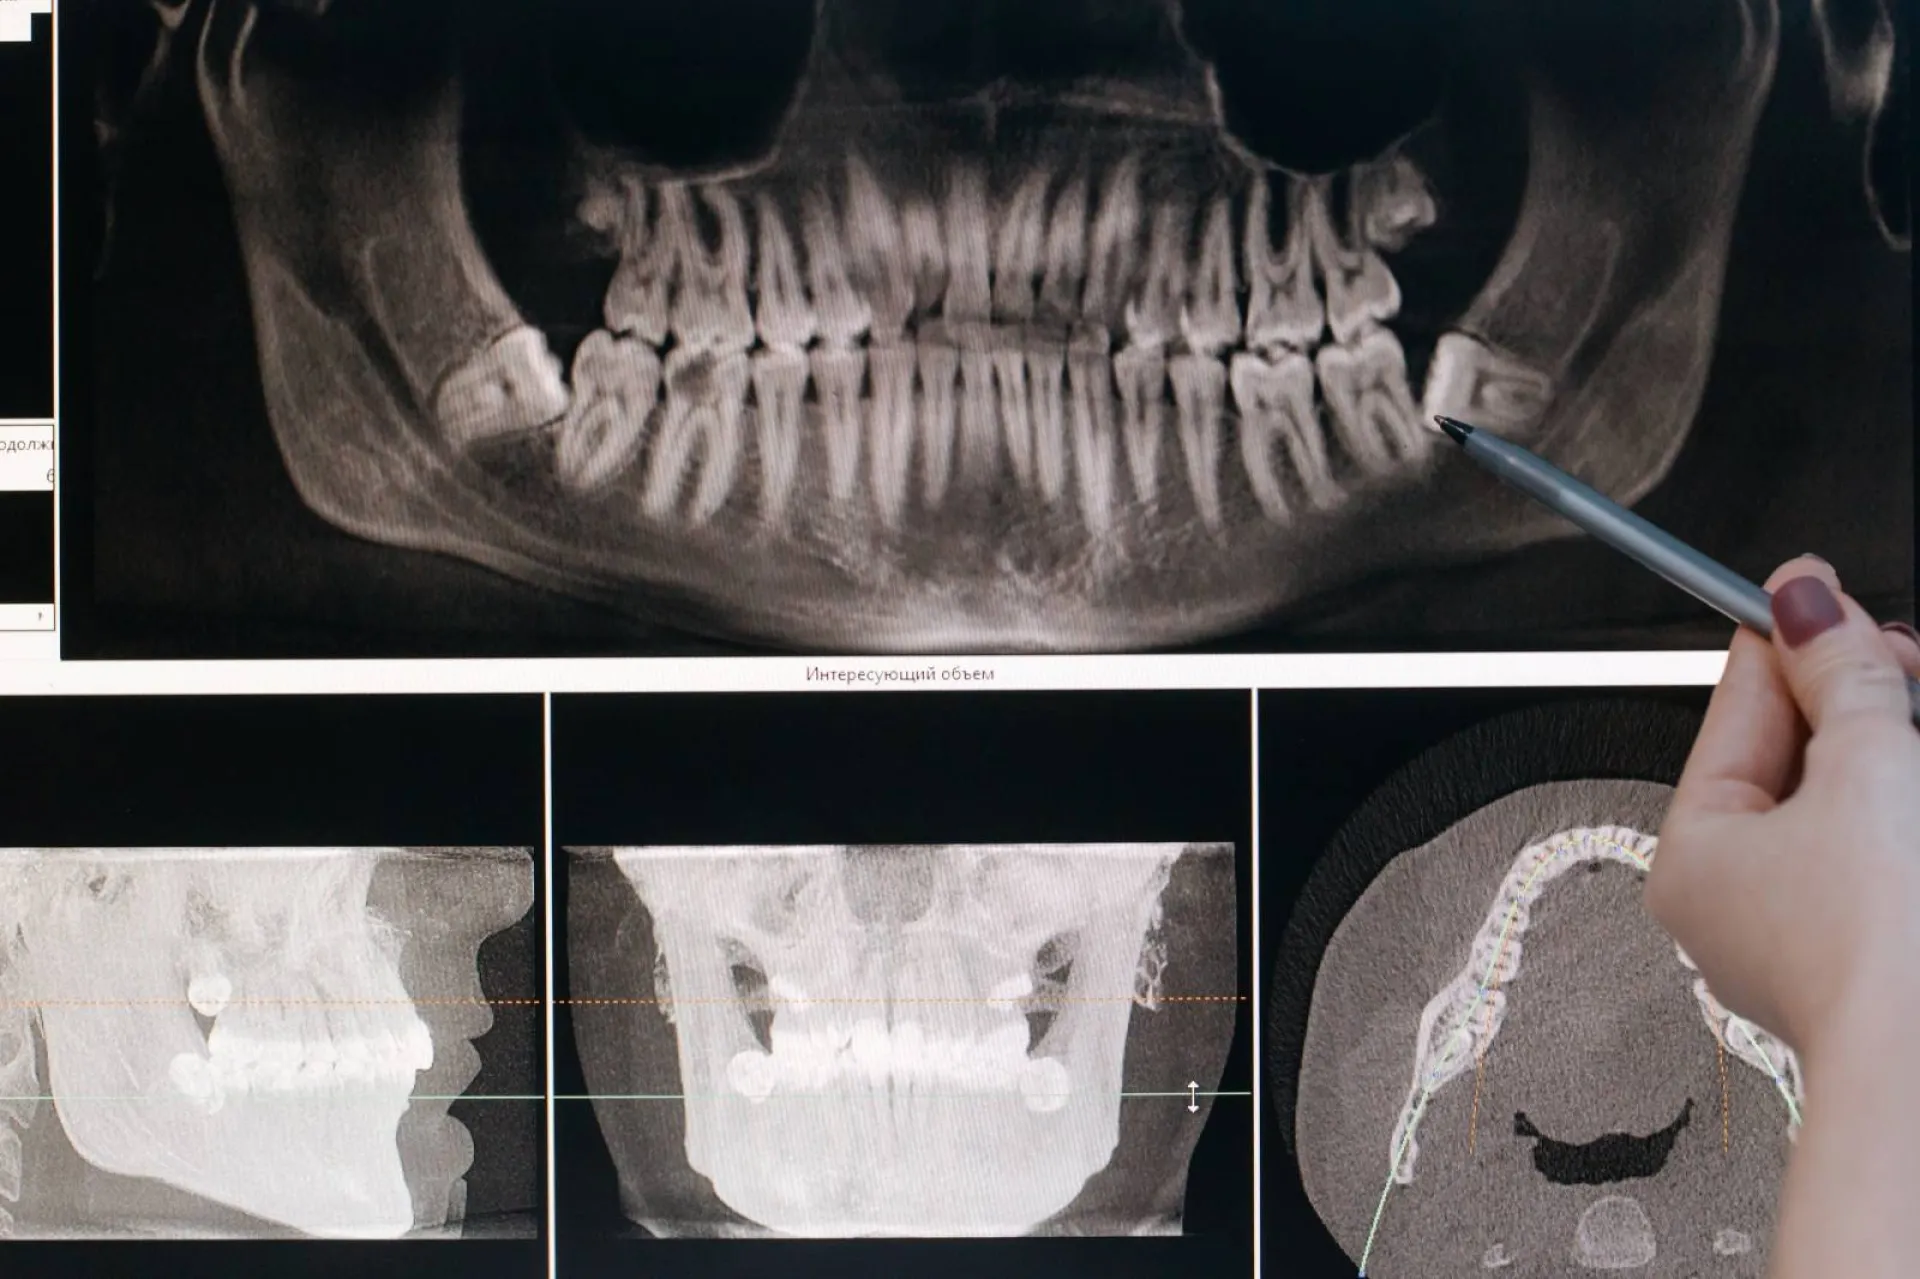

Le panoramique dentaire, ou OPG (orthopantomogramme), est un examen radiologique qui permet de visualiser en une seule image l’ensemble des dents, des mâchoires et des articulations temporo-mandibulaires. Réalisé dans un appareil à rayons X, il est indispensable pour le diagnostic bucco-dentaire, la préparation d’un traitement orthodontique ou la pose d’implants.

Examen de panoramique dentaire dans notre centre d'imagerie médicale à Marseille

La radiographie panoramique dentaire permet de réaliser une imagerie de la totalité de la dentition ainsi que des mâchoires. Elle permet de connaître le positionnement des dents ainsi que les éventuelles anomalies au contact des racines et au niveau des couronnes. Elle permet de mettre en évid...